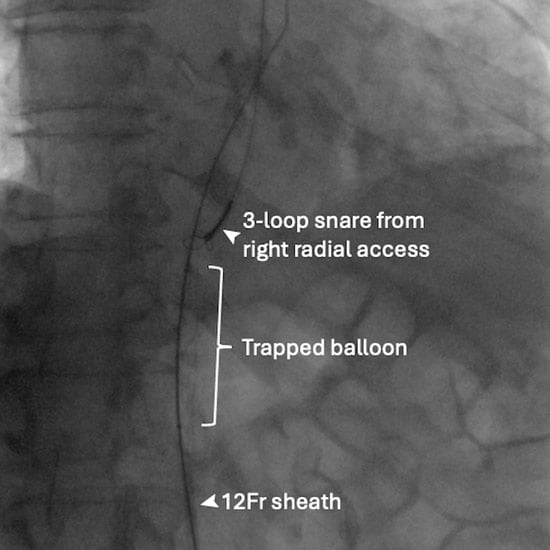

An 81-year-old male patient with symptomatic severe aortic stenosis was admitted for transcatheter aortic valve intervention via right radial and femoral accesses. The native aortic valve was predilated with a 24-mm TrueTM balloon (BD, Franklin Lakes, NJ, USA), delivered via a 12F sheath. The deflated balloon could not be retrieved. Further withdrawal resulted in concertina of the sheath (Figure 1A).

Figure 1A: Failed balloon retrieval.

Physical withdrawal of the unsheathed deflated balloon was considered and briefly attempted but was resisted, and severe damage to the calcified iliac and femoral systems was feared. Snaring of the balloon tip from the right radial access for straightening the system did not help with retrieval (Figure 1B).

Figure 1B: Snaring from right radial access.